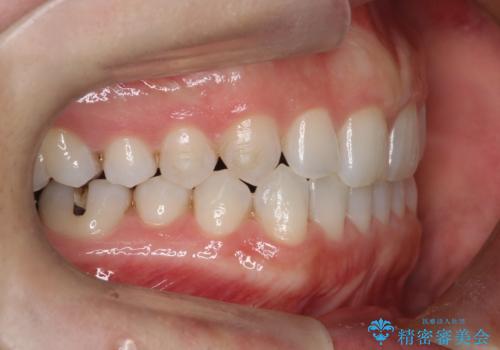

- 前歯の正中離開(すきっ歯)の改善を希望され来院された患者様です。

初診時の歯並びの状態としては、上顎中切歯間に1mm程の隙間があり、その他に見た目に関して気になるような問題点はない状態でした。

インビザライン(マウスピース)にて上顎のみの矯正治療を行いました。

見た目、嚙み合わせ及び、治療期間や施術内容に大変ご満足いただきました。